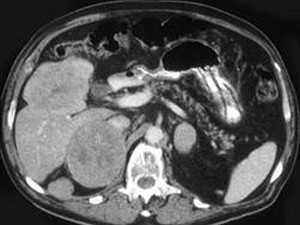

男性,60岁,曾患乙肝,肝硬化多年,右上腹胀痛1月余,AFP为80.8μg/L,CT检查如图所示,最佳的诊断是 ( ) CY-00021.jpg CY-00022.jpg

• A.肝腺瘤、右肾上腺腺瘤

• B.肝结节性增生、右肾上腺瘤

• C.肝、右肾上腺均为转移瘤

• D.肾上腺癌肝转移

• E.肝癌右肾上腺转移